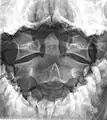

Fractures of the dens, not to be confused with Hangman's fractures, are classified into three categories according to the Anderson Alonso system:

- Type I fracture - Extends through the tip of the dens. This type is usually stable.

- Type II fracture - Extends through the base of the dens. It is the most commonly encountered fracture for this region of the axis. This type is unstable and has a high rate of non-union.

- Type III fracture - Extends through the vertebral body of the axis. This type can be stable or unstable and may require surgery.

Type 2 dens fracture